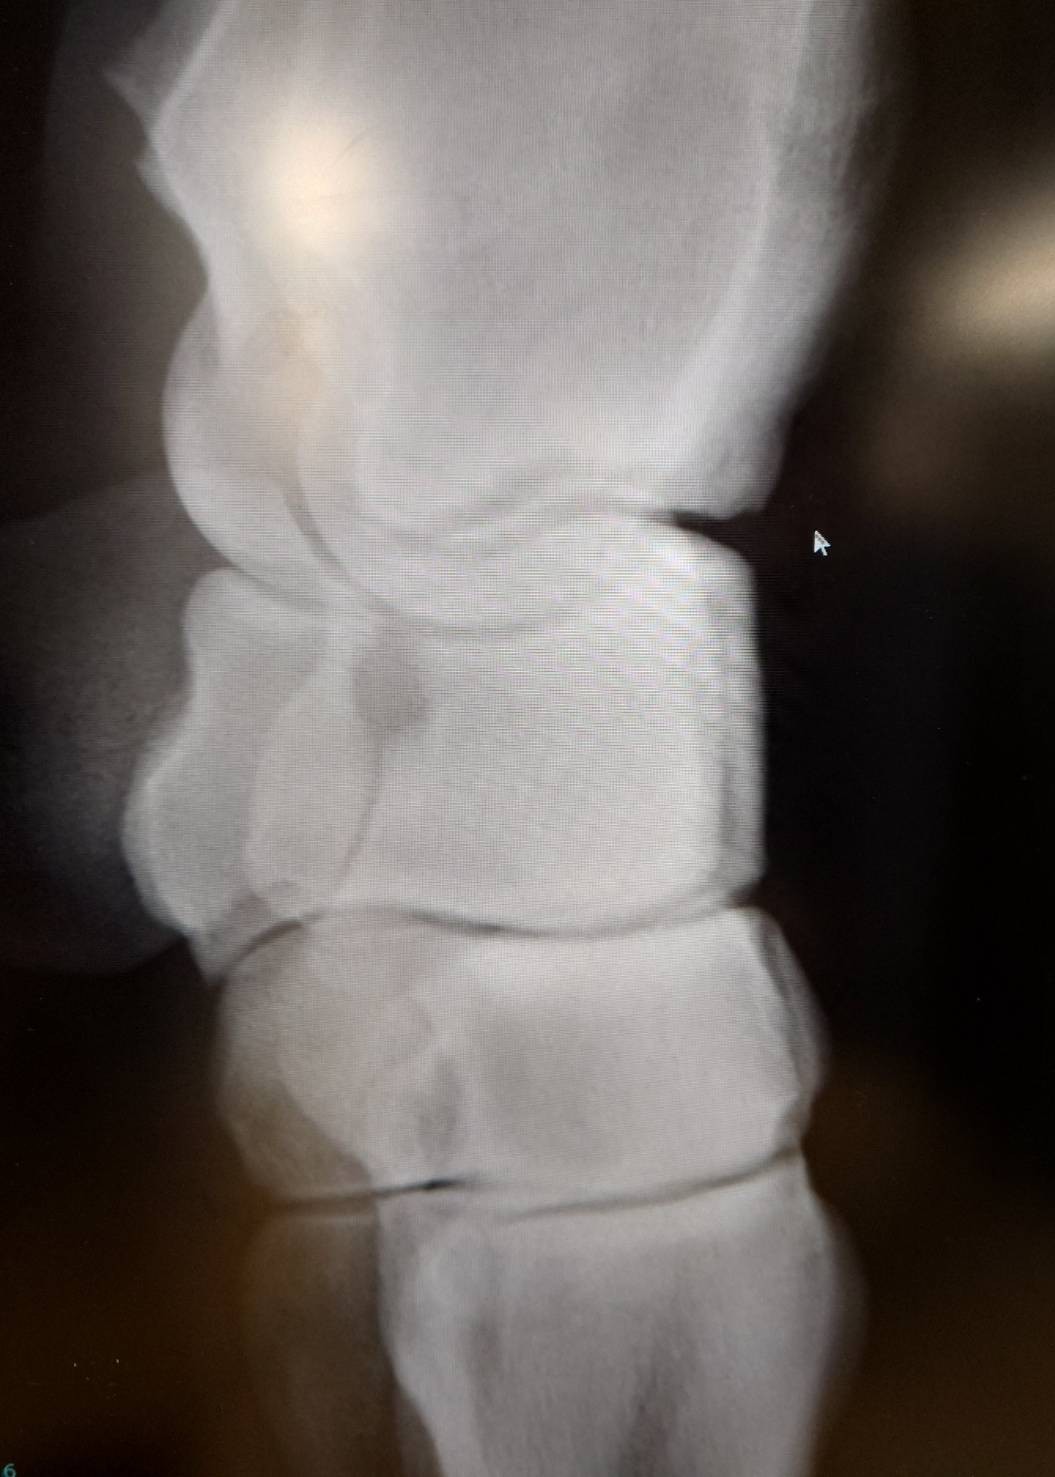

※2026年2月10日京都2R出走後、左膝が腫れたことからレントゲン撮影を行ったところ、左前橈骨遠位端剥離骨折が判明。事故見舞金9号(競走中の事故により事故発生の日から6カ月以上出走できなくなった場合)の適用を受けています。